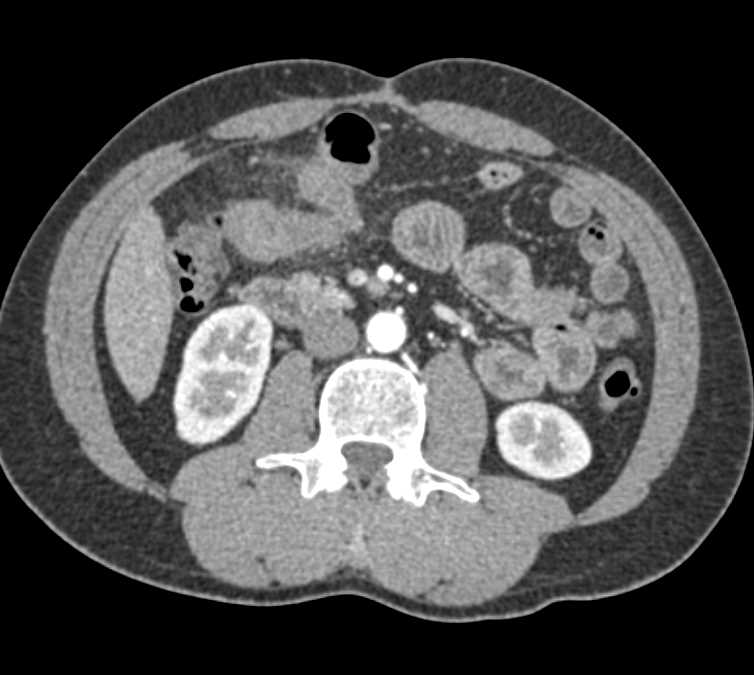

Small Bowel Obstruction (SBO) with Thickened Small Bowel Folds